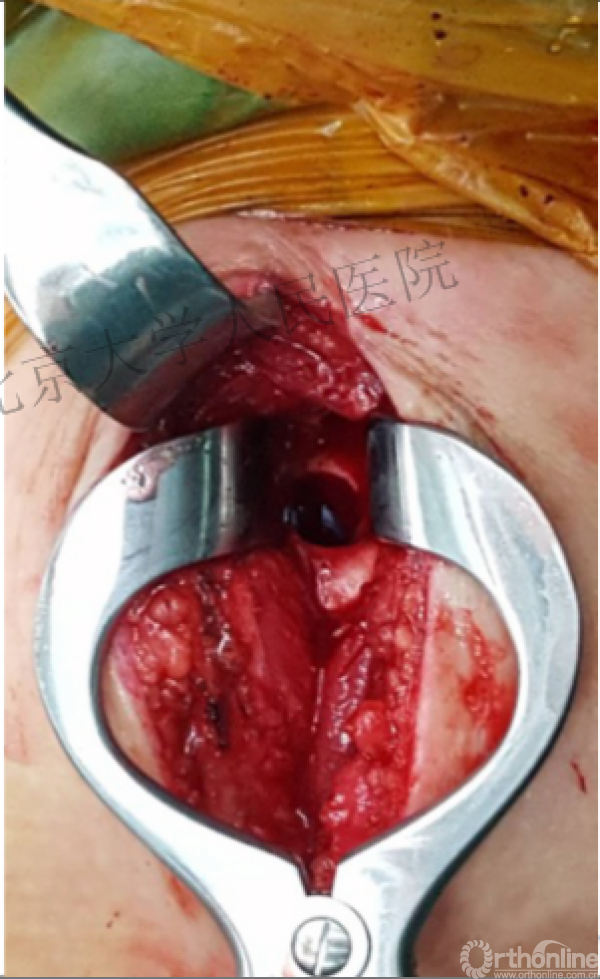

切口后通过结节间沟判断头的方位

体会:避免肩袖医原损伤的经验方法

消除肩袖损伤顾虑

视野更清楚

操作更加容易